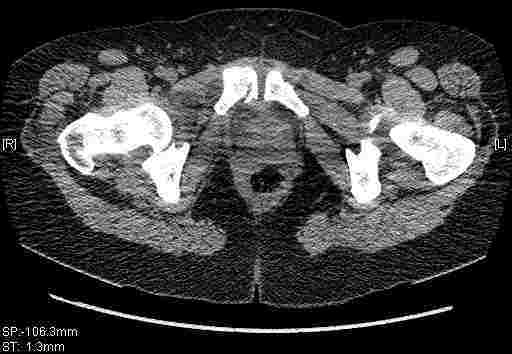

Удалось сегодня вывести пациентку в соседнюю больницу, где есть кт. Срезы сделаны только горизонтальные.

|